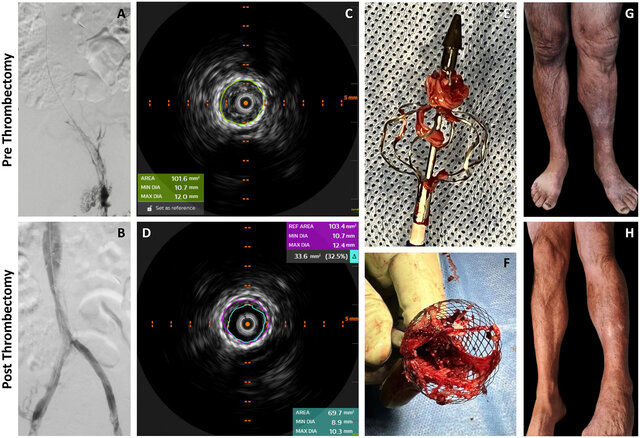

- Surgical intervention: thrombectomy